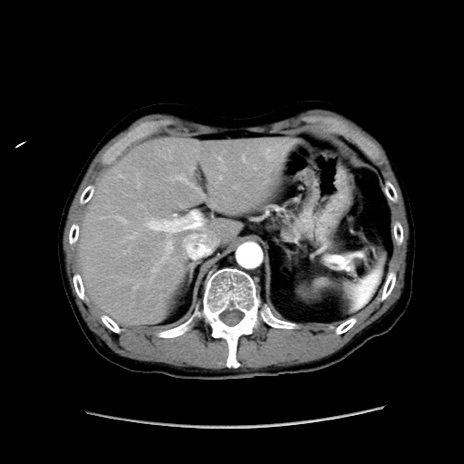

症例37(横断像)

【症例】40歳代 男性

【主訴】腹痛

【現病歴】4時間ほど前に電車に乗車中に臍部上より腹痛出現。徐々に増悪し起立困難となり、救急外来受診。生ものは数日食べていない。今朝お雑煮を食べた。

【身体所見】BT 36.8℃、BP 117/84mmHg、HR 91/min、SpO2 97%、苦悶様、腹部:臍上部広範囲圧痛あり、反跳痛±

【データ】WBC 8100、CRP 0.03